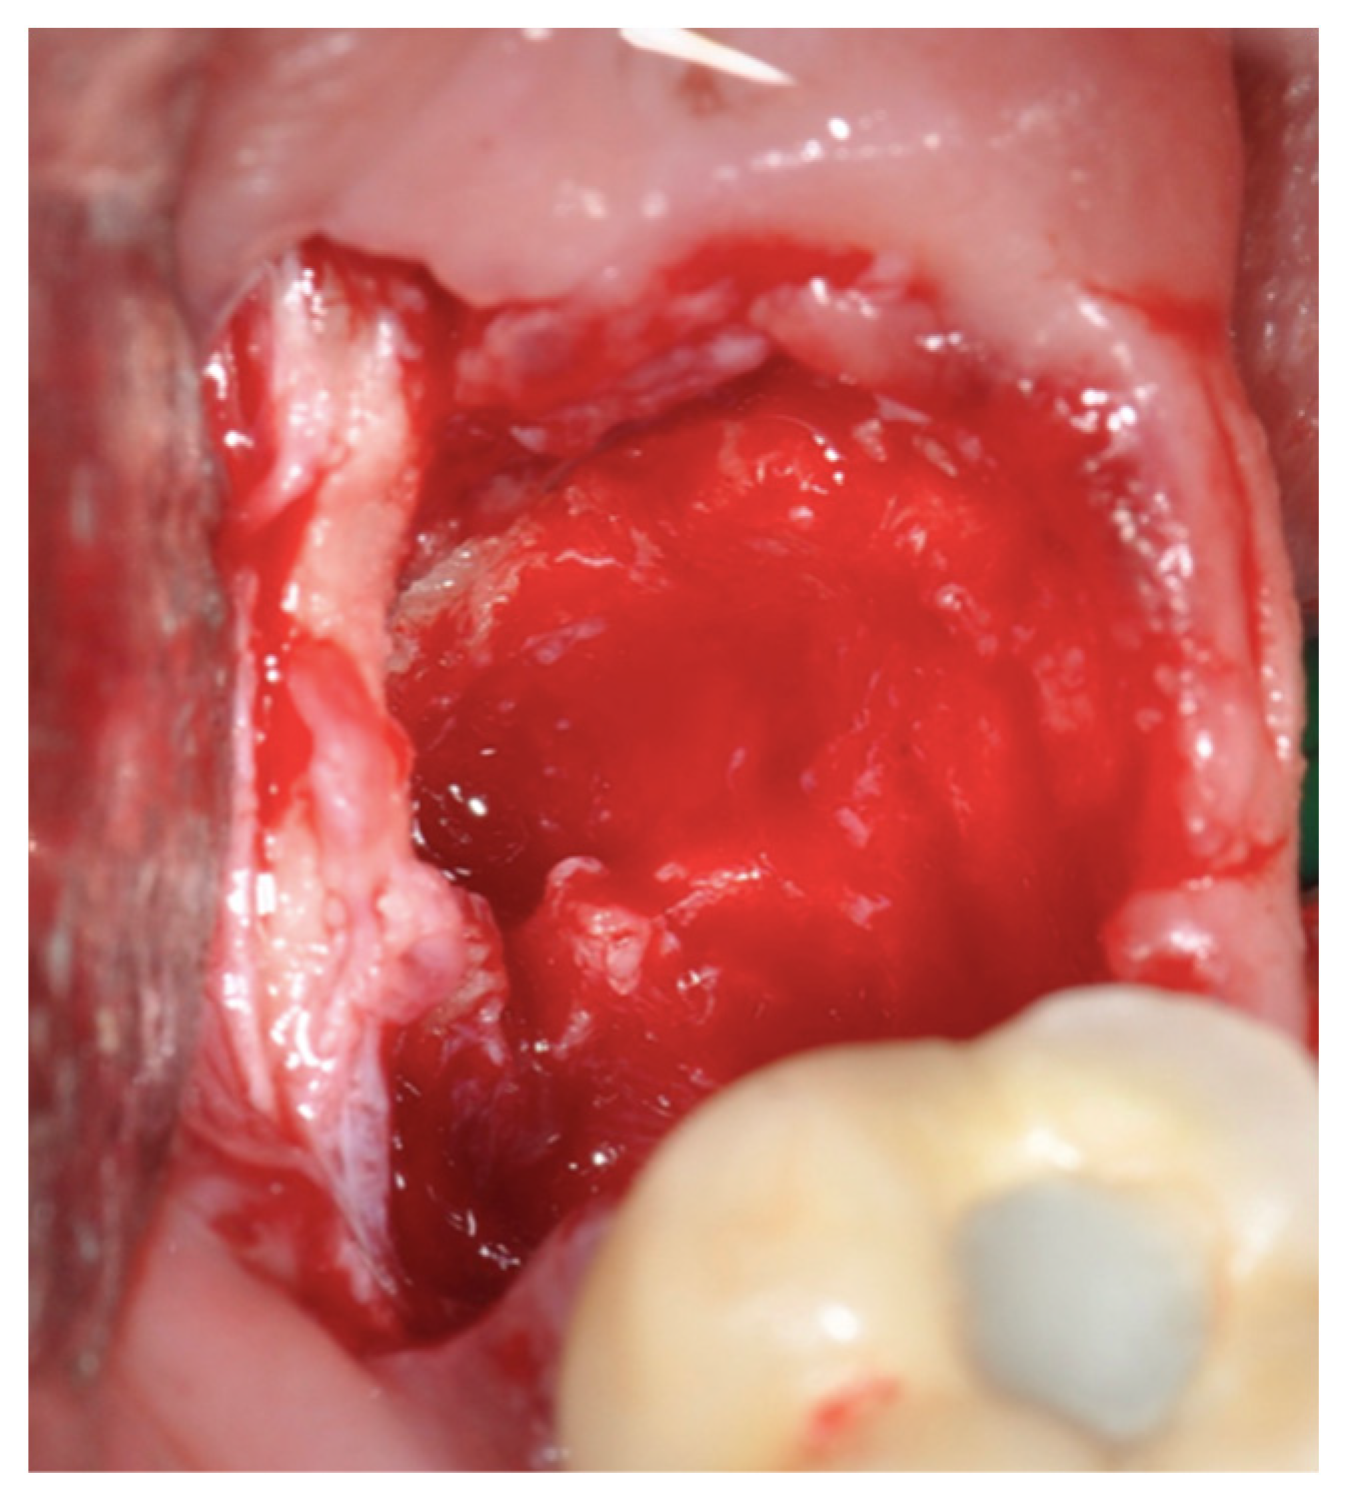

2.2. Surgical Technique